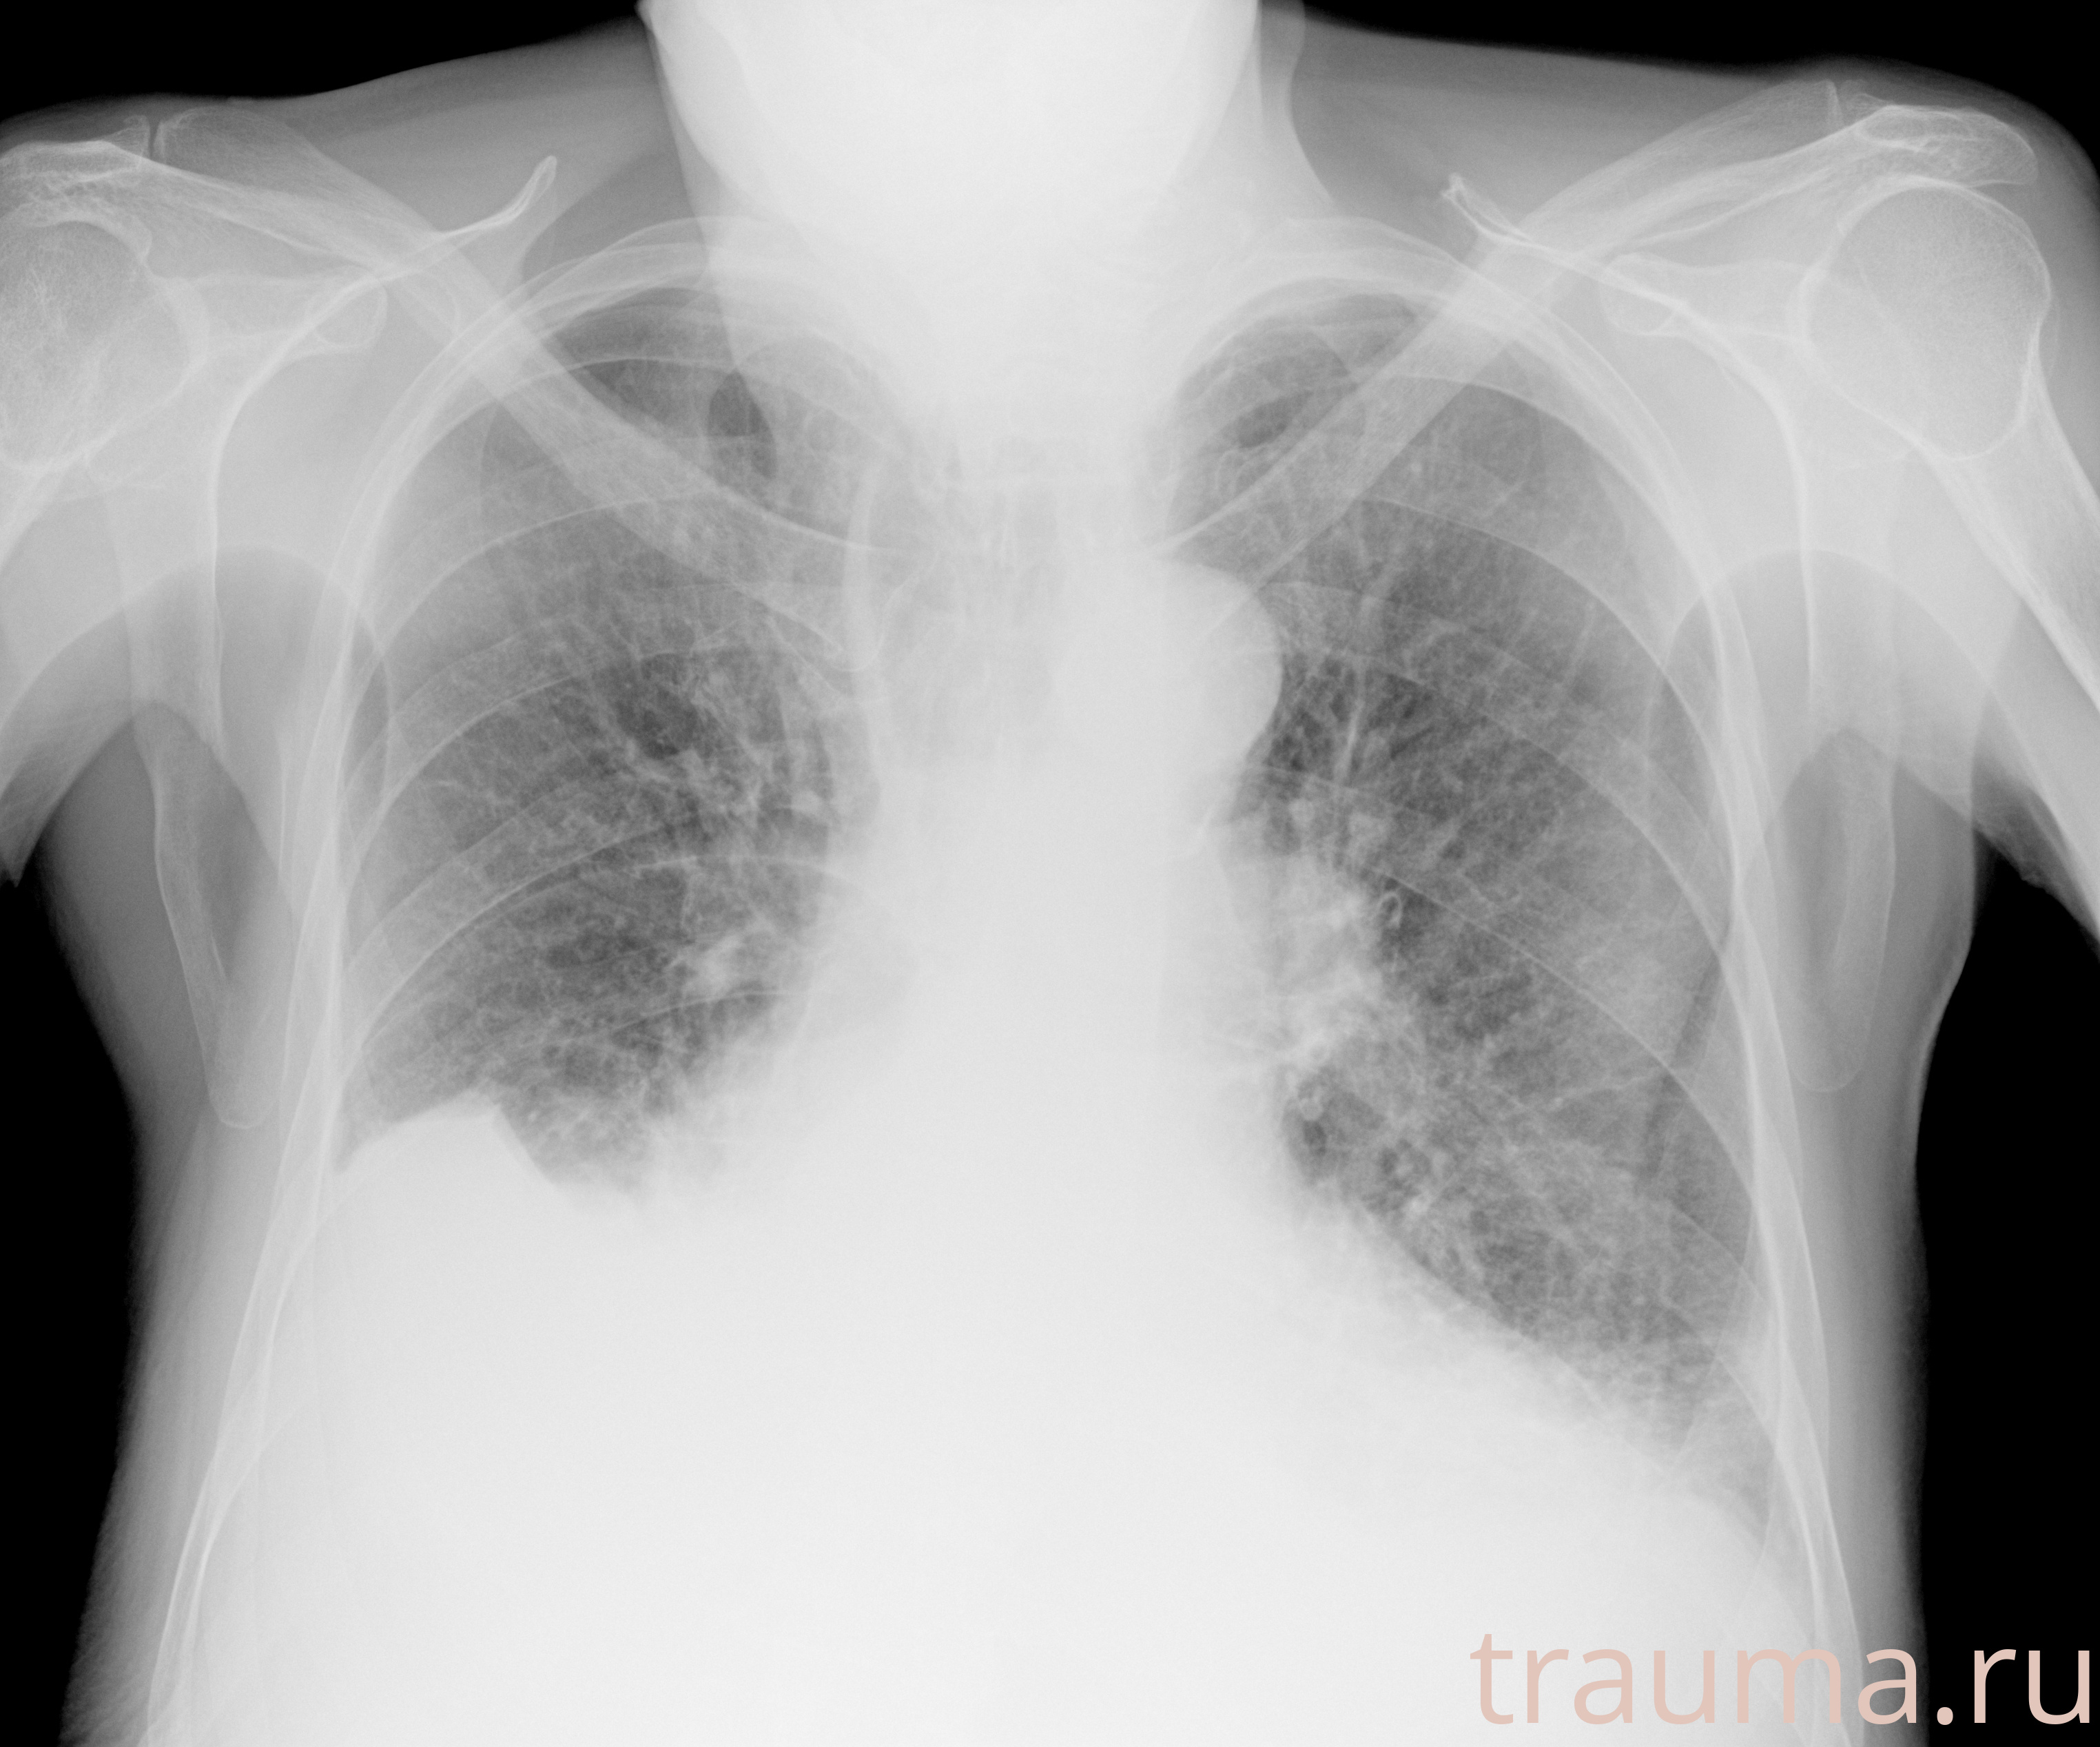

Рентгенограммы

Рентген на дому: по вашему адресу приезжает врач-рентгенолог, травматолог-ортопед с мобильным рентгеновским аппаратом, проводит диагностику травмы или заболевания, делает необходимые рентгенограммы, дает рекомендации по дальнейшему лечению. Получить качественные снимки в домашних условиях возможно благодаря уникальной методике, разработанной МосРентген Центром для института  Склифосовского

при переломе шейки бедра и пневмонии от компании МосРентген Центр - партнера Института имени Склифосовского